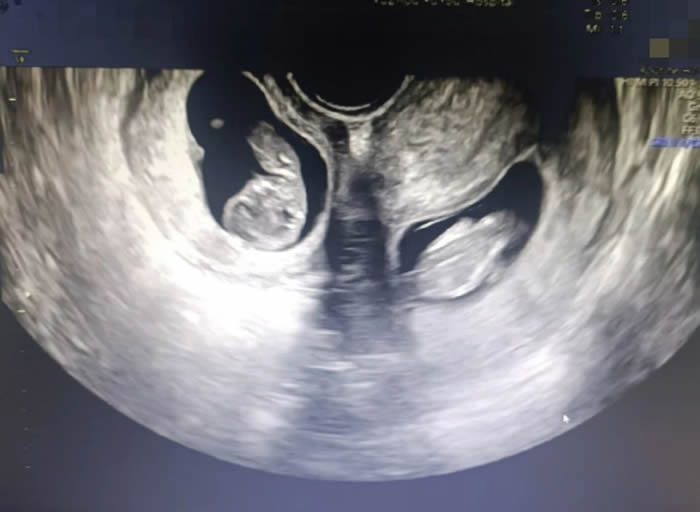

各科醫護配合默契,主刀醫(yī)生沙小龍手法(fǎ)嫻熟,開腹、取子一氣(qì)嗬成。手術(shù)開始(shǐ)僅4分鍾,伴隨(suí)著一(yī)聲清(qīng)脆的啼哭,第一(yī)個孩子(zǐ)成(chéng)功取出,女孩,1.6千克,2分鍾後,男孩出(chū)生(shēng),體重2.03千克。

早(zǎo)早等(děng)在一旁的新生(shēng)兒(ér)科(kē)醫生立刻為兩(liǎng)個孩子進行檢查,隨後轉入新生兒病房進行救治。為了預防產後出血,取出龍鳳胎後,沙小龍醫生第一時間用藥促進子宮(gōng)及時收縮,兩(liǎng)個子宮緊(jǐn)緊貼在一起,形成了一個完(wán)整的心型。